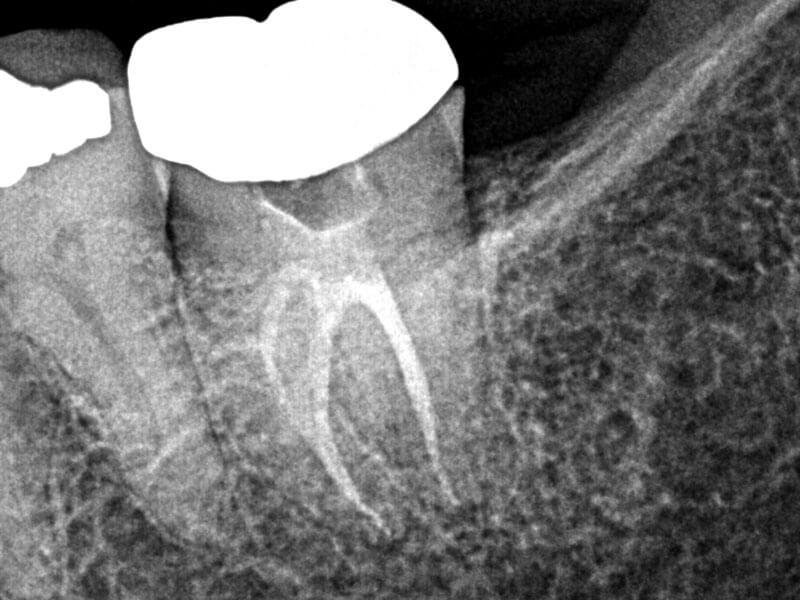

#18 Pulpal Necrosis and Normal Periapex

66-year-old female presented with history of spontaneous, intermittent pain in the lower left quadrant for three days, progressing to acute pain. No hot, cold or biting pain. Clinical testing revealed teeth in LLQ were negative to percussion, biting and grinding. Tooth #18 tested negative to cold, and other teeth in quadrant tested within normal limits to cold. Diagnosis: #18 necrosis and normal periapex. Treatment plan: RCT #18. Accessed, working length established, SlimShaper® ZS1 and ZS2 in distal canal and one mesial canal. Other mesial canal would not permit rotaries due to angle, so employed #15 hand file to length. GentleWave® Procedure with ProControl™ completed. Obturated with TruNatomy® 20 GP and BC Sealer HiFlow™. BC Liner™ over orifices.

Pre

Post